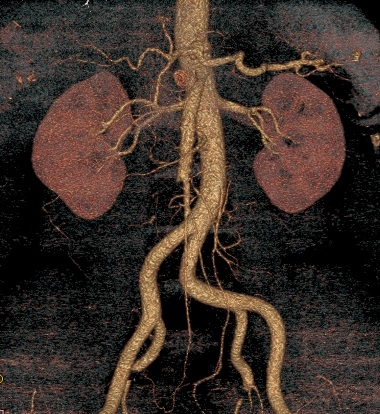

Acute abdominal pain is one of the most common conditions encountered in the emergency department. The differential diagnosis of acute abdominal pain is extensive and identifying the underlying etiology can be challenging. We report a case of acute transient ischemic jejunitis due to symptomatic isolated superior mesenteric artery dissection in a patient with no cardiovascular risk factors or autoimmune diseases. Symptomatic isolated superior mesenteric artery dissection is a rare cause of acute abdominal pain usually treated in the surgical department. The patient had criteria for conservative treatment and rapidly recovered. We highlight a rare condition which should be taken into account for the differential diagnosis of acute abdominal pain.